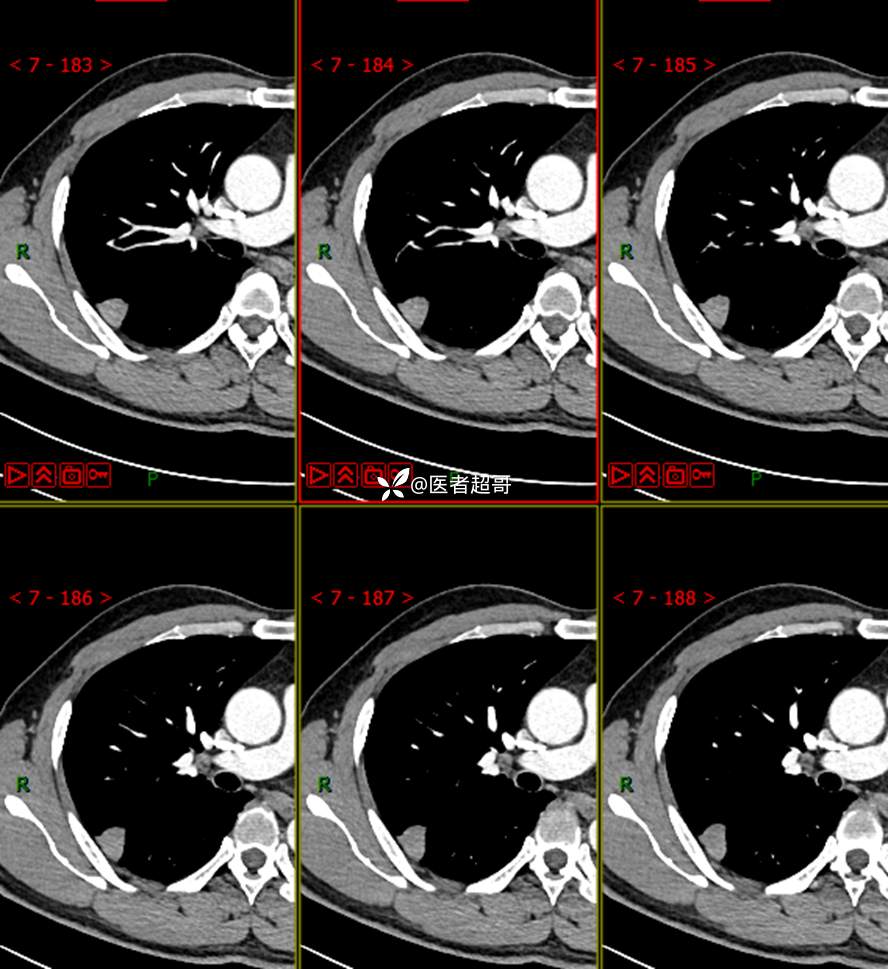

现病史:患者1年余前于体健中心行胸部X片发现右上肺叶密度增高影,无明显咳嗽,咳痰,无痰中带血及咯血,无胸痛及胸闷、气短,无发热、盗汗及全身乏力。无头痛、头晕,无腹痛、腹胀及恶心、呕吐,无声音嘶哑及呛咳,未行特殊治疗。后患者定期复查胸部CT,未见明显变化。2023-2-6患者于我院复查胸部CT:右肺上叶、下叶交接处胸膜下见实性结节影,最大截面约2.6cm×1.4cm,较前增大,建议行手术治疗。今为求进一步诊治,遂来我院就诊,门诊以“肺肿物”收入我院,患者自发病以来,神志清,精神可,饮食可,睡眠良好,大小便正常,近期体重未见明显增减。